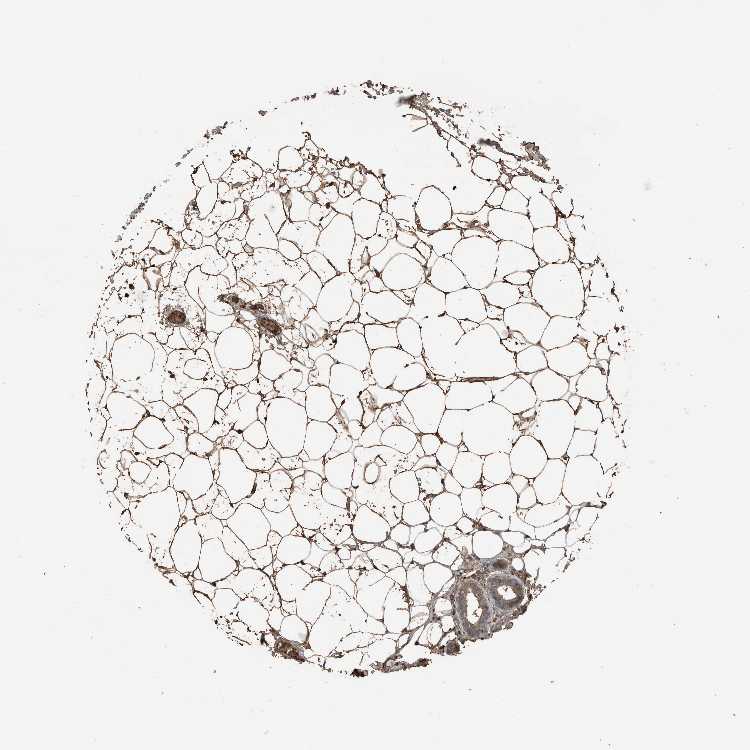

ADIPOSE TISSUE - Antibody stainingi

Antibody staining in the annotated cell types in the current human tissue is reported as not detected, low, medium, or high, based on conventional immunohistochemistry profiling in selected tissues. This score is based on the combination of the staining intensity and fraction of stained cells.

Each image is clickable and will lead to virtual microscopy that enables deeper exploration of all samples and also displays staining intensity scores, fraction scores and subcellular localization as well as patient and tissue information for each sample.

Antibody HPA025815

Adipocytes Medium